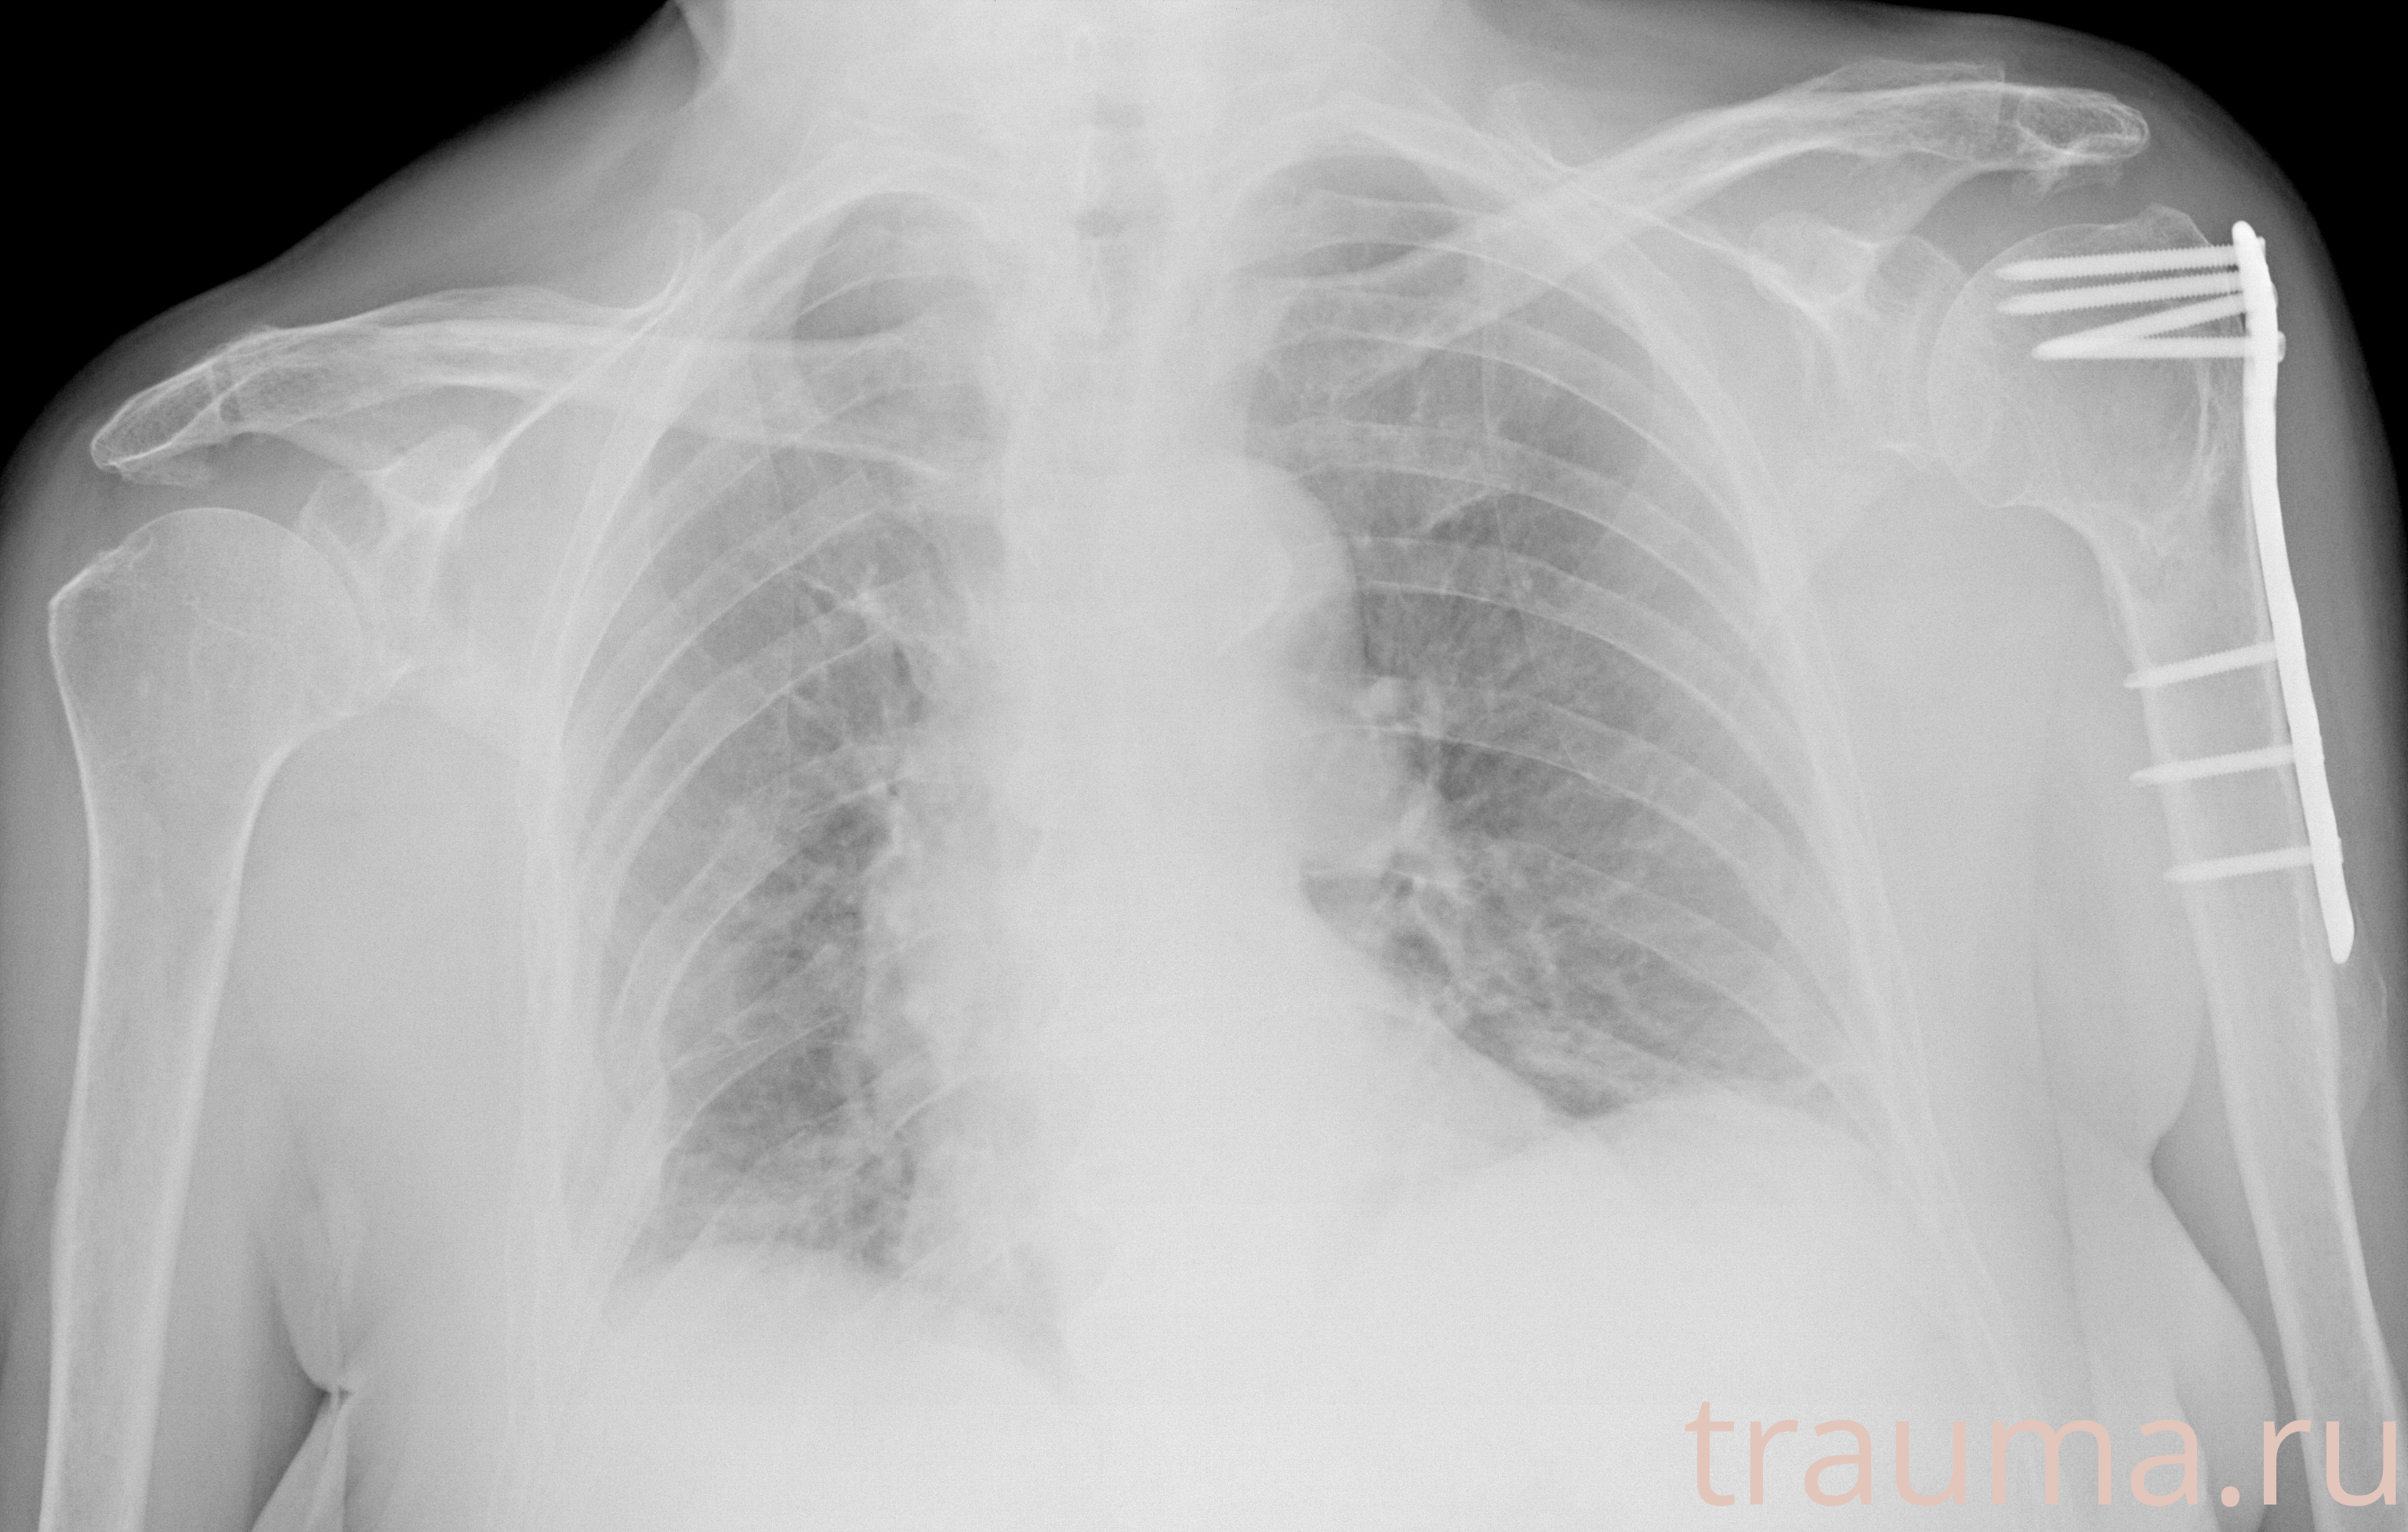

Рентген на дому: по вашему адресу приезжает врач-рентгенолог, травматолог-ортопед с мобильным рентгеновским аппаратом, проводит диагностику травмы или заболевания, делает необходимые рентгенограммы, дает рекомендации по дальнейшему лечению. Получить качественные снимки в домашних условиях возможно благодаря уникальной методике, разработанной МосРентген Центром для института  Склифосовского